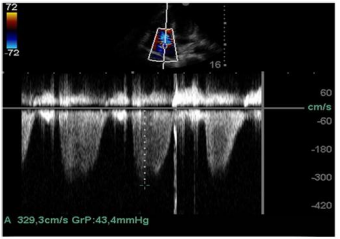

Ainda com o uso da ecocardiografia beira-leito, realizou-se a mensuração da pressão sistólica do ventrículo direito por meio da análise do refluxo tricuspídeo demonstrando o valor de 43,4 mmHg, como apresentado na imagem.

Também foi feita a mensuração da cava na janela subcostal 4 câmaras caval. O seu valor é maior de 2,2 cm e tem variabiliadade menor que 50% aos movimentos respiratórios ainda em ventilação espontânea, conforme a imagem apresentada.

Com base nessas informações e nas imagens, a estimativa da pressão sistólica da artéria pulmonar é de